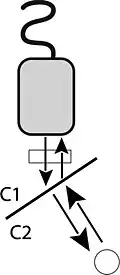

Refração

Refração é o fenômeno de mudança de direção da onda sonora transmitida em uma fronteira entre dois tecidos quando o feixe incidente não é perpendicular a esta fronteira. A frequência da onda incidente não se altera, mas a velocidade do som pode ser diferente nos dois tecidos. O ângulo de refração é dado pela Lei de Snell:

sendo e os ângulos incidente e transmitido, quando a onda sonora se propaga do meio 1 para o meio 2, com velocidades do som no meio iguais a e , respectivamente.

A ocorrência de refração em ultrassonografia resulta em artefatos,[13] como o da imagem ao lado. O feixe de ultrassom incidente sofre refração e encontra duas estruturas. Ao construir a imagem, o objeto no caminho do feixe refratado estará posicionado no lugar incorreto, pois o display do ultrassom assume que o feixe se propaga por um caminho reto.

Não ocorre refração quando a velocidade do som é a mesma nos dois tecidos, ou quando a incidência é perpendicular.